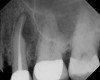

Figure 4  Clinical case of a lack of coronal seal that contributed to the failure of this root canal treatment.

Figure 4